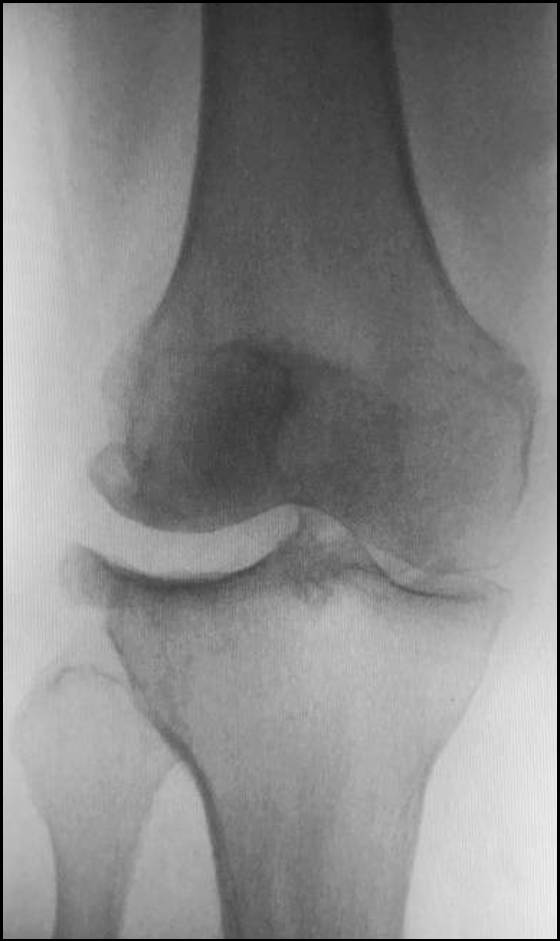

女性患者,69 岁,右膝关节疼痛伴活动受限 5 年余。

体格检查:右膝外翻畸形,约6°,无屈曲畸形。屈曲20°内翻应力下外翻畸形可纠正,屈曲90°可自行纠正。外侧关节间隙处压痛阳性。活动度:0°~115°。

X-Ray:右膝外侧间隙明显狭窄,站立位外侧间隙消失,内侧间隙正常,膝关节稳定。

诊断:右膝关节外侧间室OA。